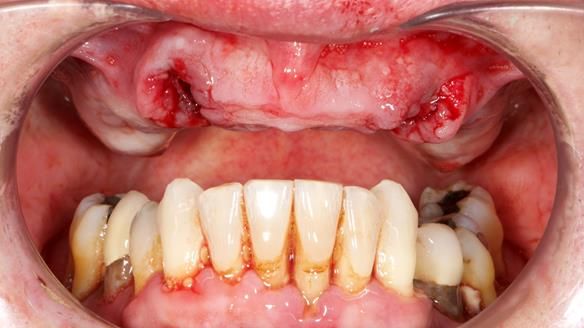

- The upper molars (UR7 and UL7) had also failed and required removal.

- Extract the failed molars and dismantle the bridge.

Initially, the plan was to retain the canine roots (13 and 23) under the denture after root canal treatment, as set out in the original treatment plan letter.